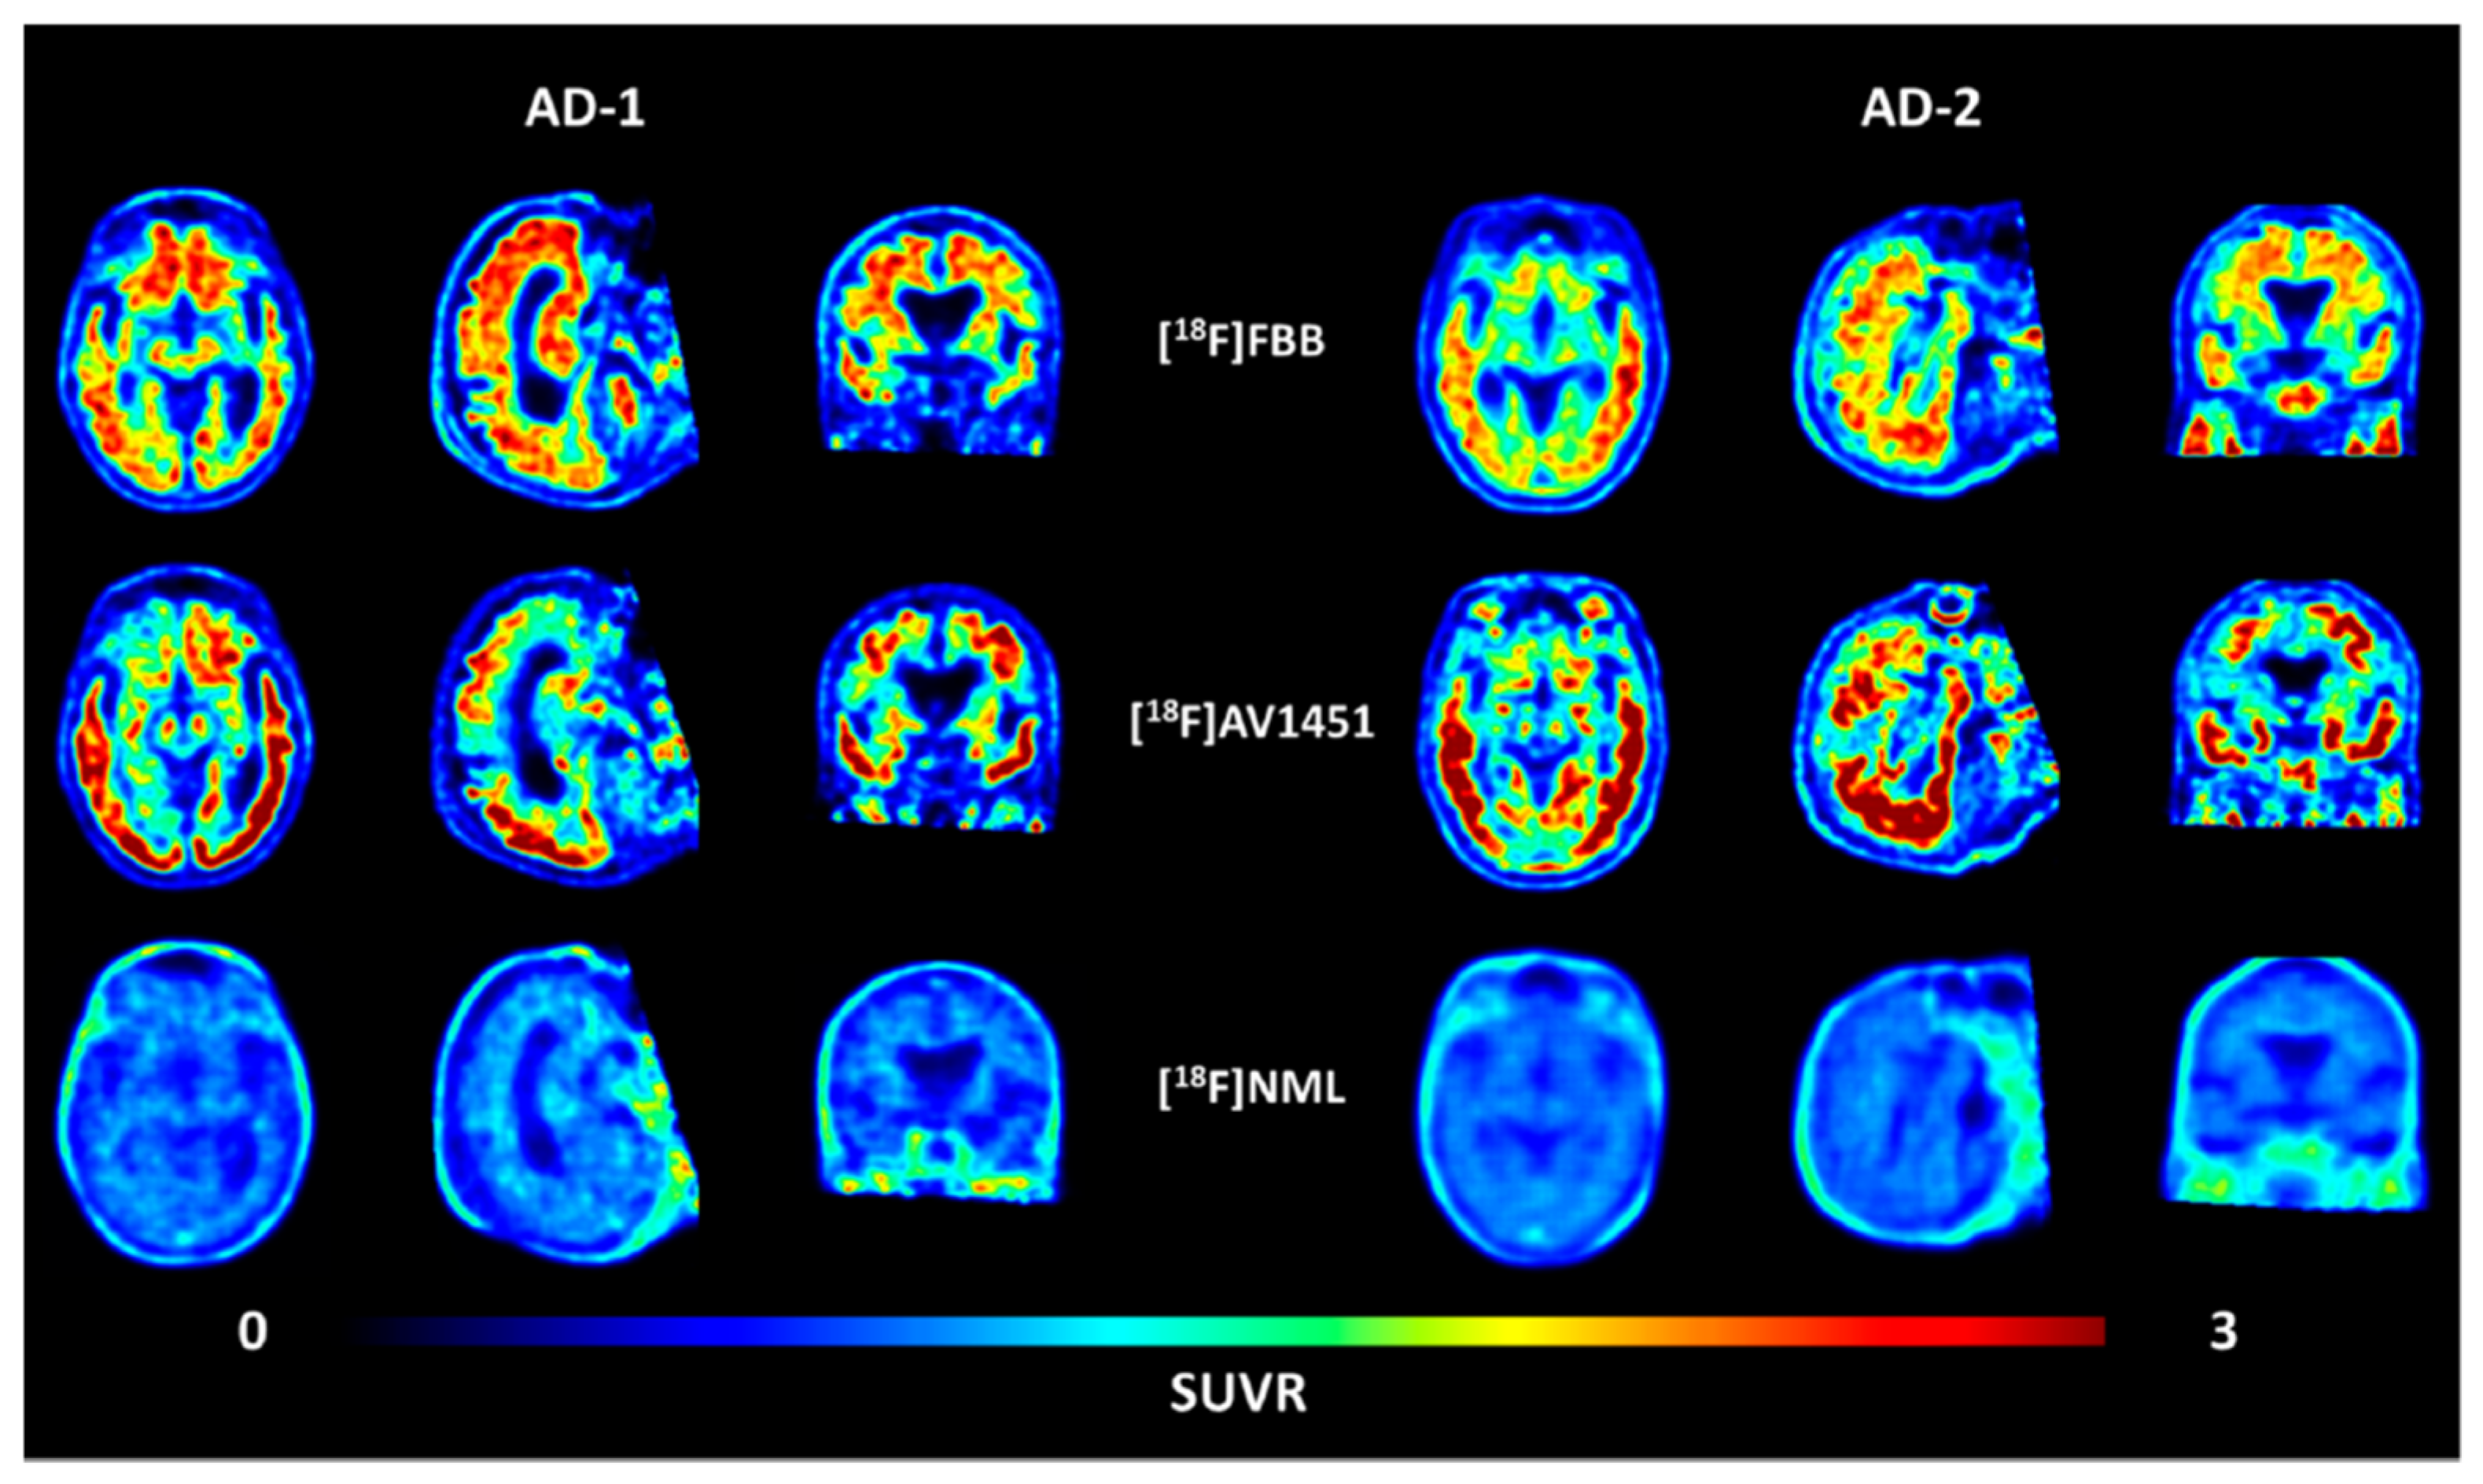

- Kramer, V.; Brooks, A.F.; Haeger, A.; Kuljis, R.O.; Rafique, W.; Koeppe, R.A.; Raffel, D.M.; Frey, K.A.; Amaral, H.; Scott, P.J.H.; et al. Evaluation of [18F]-N-Methyl Lansoprazole as a Tau PET Imaging Agent in First-in-Human Studies. ACS Chem. Neurosci. 2020, 11, 427–435. [Google Scholar] [CrossRef] [PubMed]